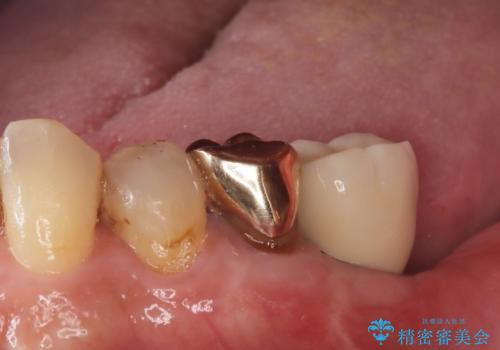

残根状態の歯を抜歯後、抜歯窩の治癒を待ちインプラントを埋入しています。

アバットメントの材質は咬合力を考慮しチタン合金にしました。

被せ物はオールセラミッククラウンを入れています。

患者さんから、インプラント埋入オペ後も痛みが殆どなく、咬めるようになったので治療をして良かったですと言って頂けました。